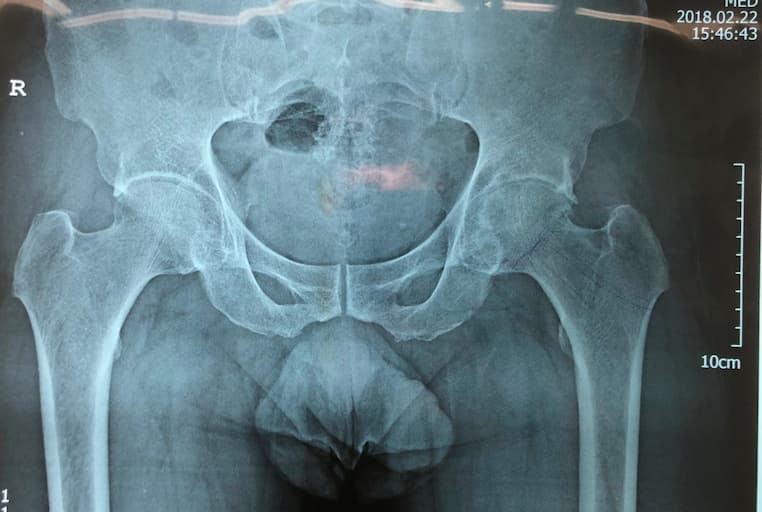

Түнхний үений төрөлхийн мултрал дутуу хөгжилтэй өвчтөний мэс заслын өмнөх болон дараах рентген зураг

Түнхний үе бүтэн солих мэс засал (THA) image3Түнхний үе бүтэн солих мэс засал (THA) image4